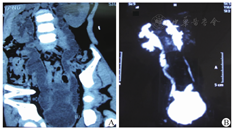

25例气膀胱Cohen组及全部改良乳头式再植术组病例,术后4~8周拔除双J管时同时行膀胱造影(图3)。改良乳头式再植组只发现2例有反流,但拔管前后并无泌尿系感染症状,查尿常规正常,而且3个月后再次造影检查均发现反流消失,考虑是大年龄儿童置入6F双J管,刚拔管时输尿管末端尚处于开放状态所致,而经过一段时间正常收缩后造影无反流。所有病例输尿管扩张均有减轻、部分恢复正常(图4),说明效果可靠,输尿管包埋在膀胱壁内1~1.5 cm没有梗阻表现。